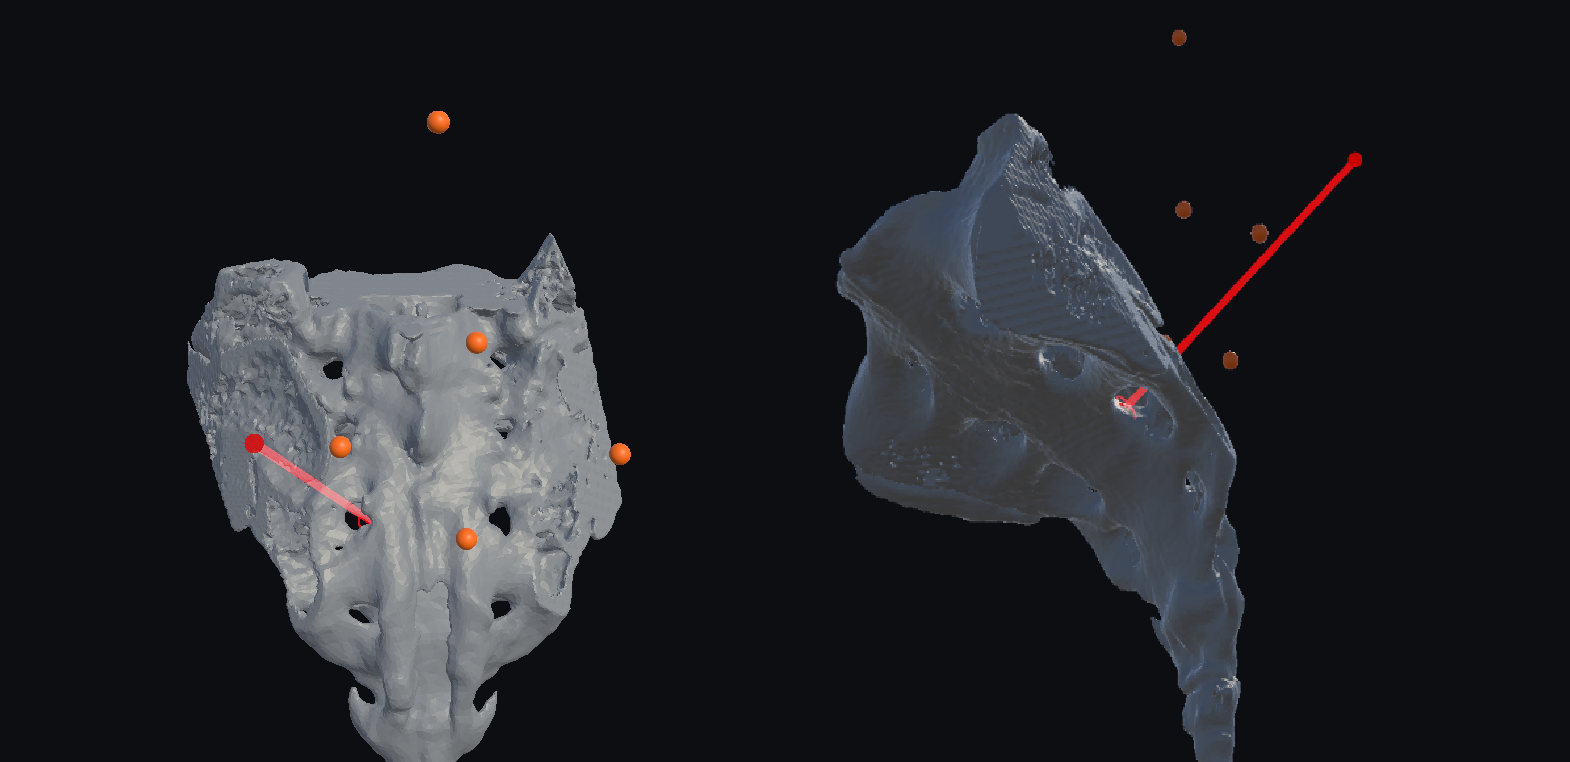

Сегментация и построение трехмерной модели крестца и черепа выполнялись с использованием программы Inobitec DICOM Viewer. (Рисунок 2)

Рисунок 2. Создание 3D модели и её сегментация в Inobitec DICOM Viewer для последующей обработки. Слева – 3D реконструкция интраоперационного КТ. Справа – сегментированная модель поверхности крестца.

Рисунок 4. Запланированная траектория для SNRS на 3D- модели крестца пациента.

Рисунок 6. Запланированная траектория имплантации электрода для SPGS.